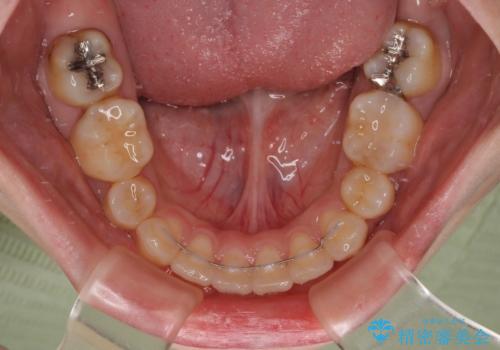

骨格的な左右差がありましたが、何とか当初予定していた期間で、左右対称の咬み合わせに仕上げることができました。

- 矯正治療後の保定が不十分だと後戻り(元の位置に戻ろうとする動き)をします